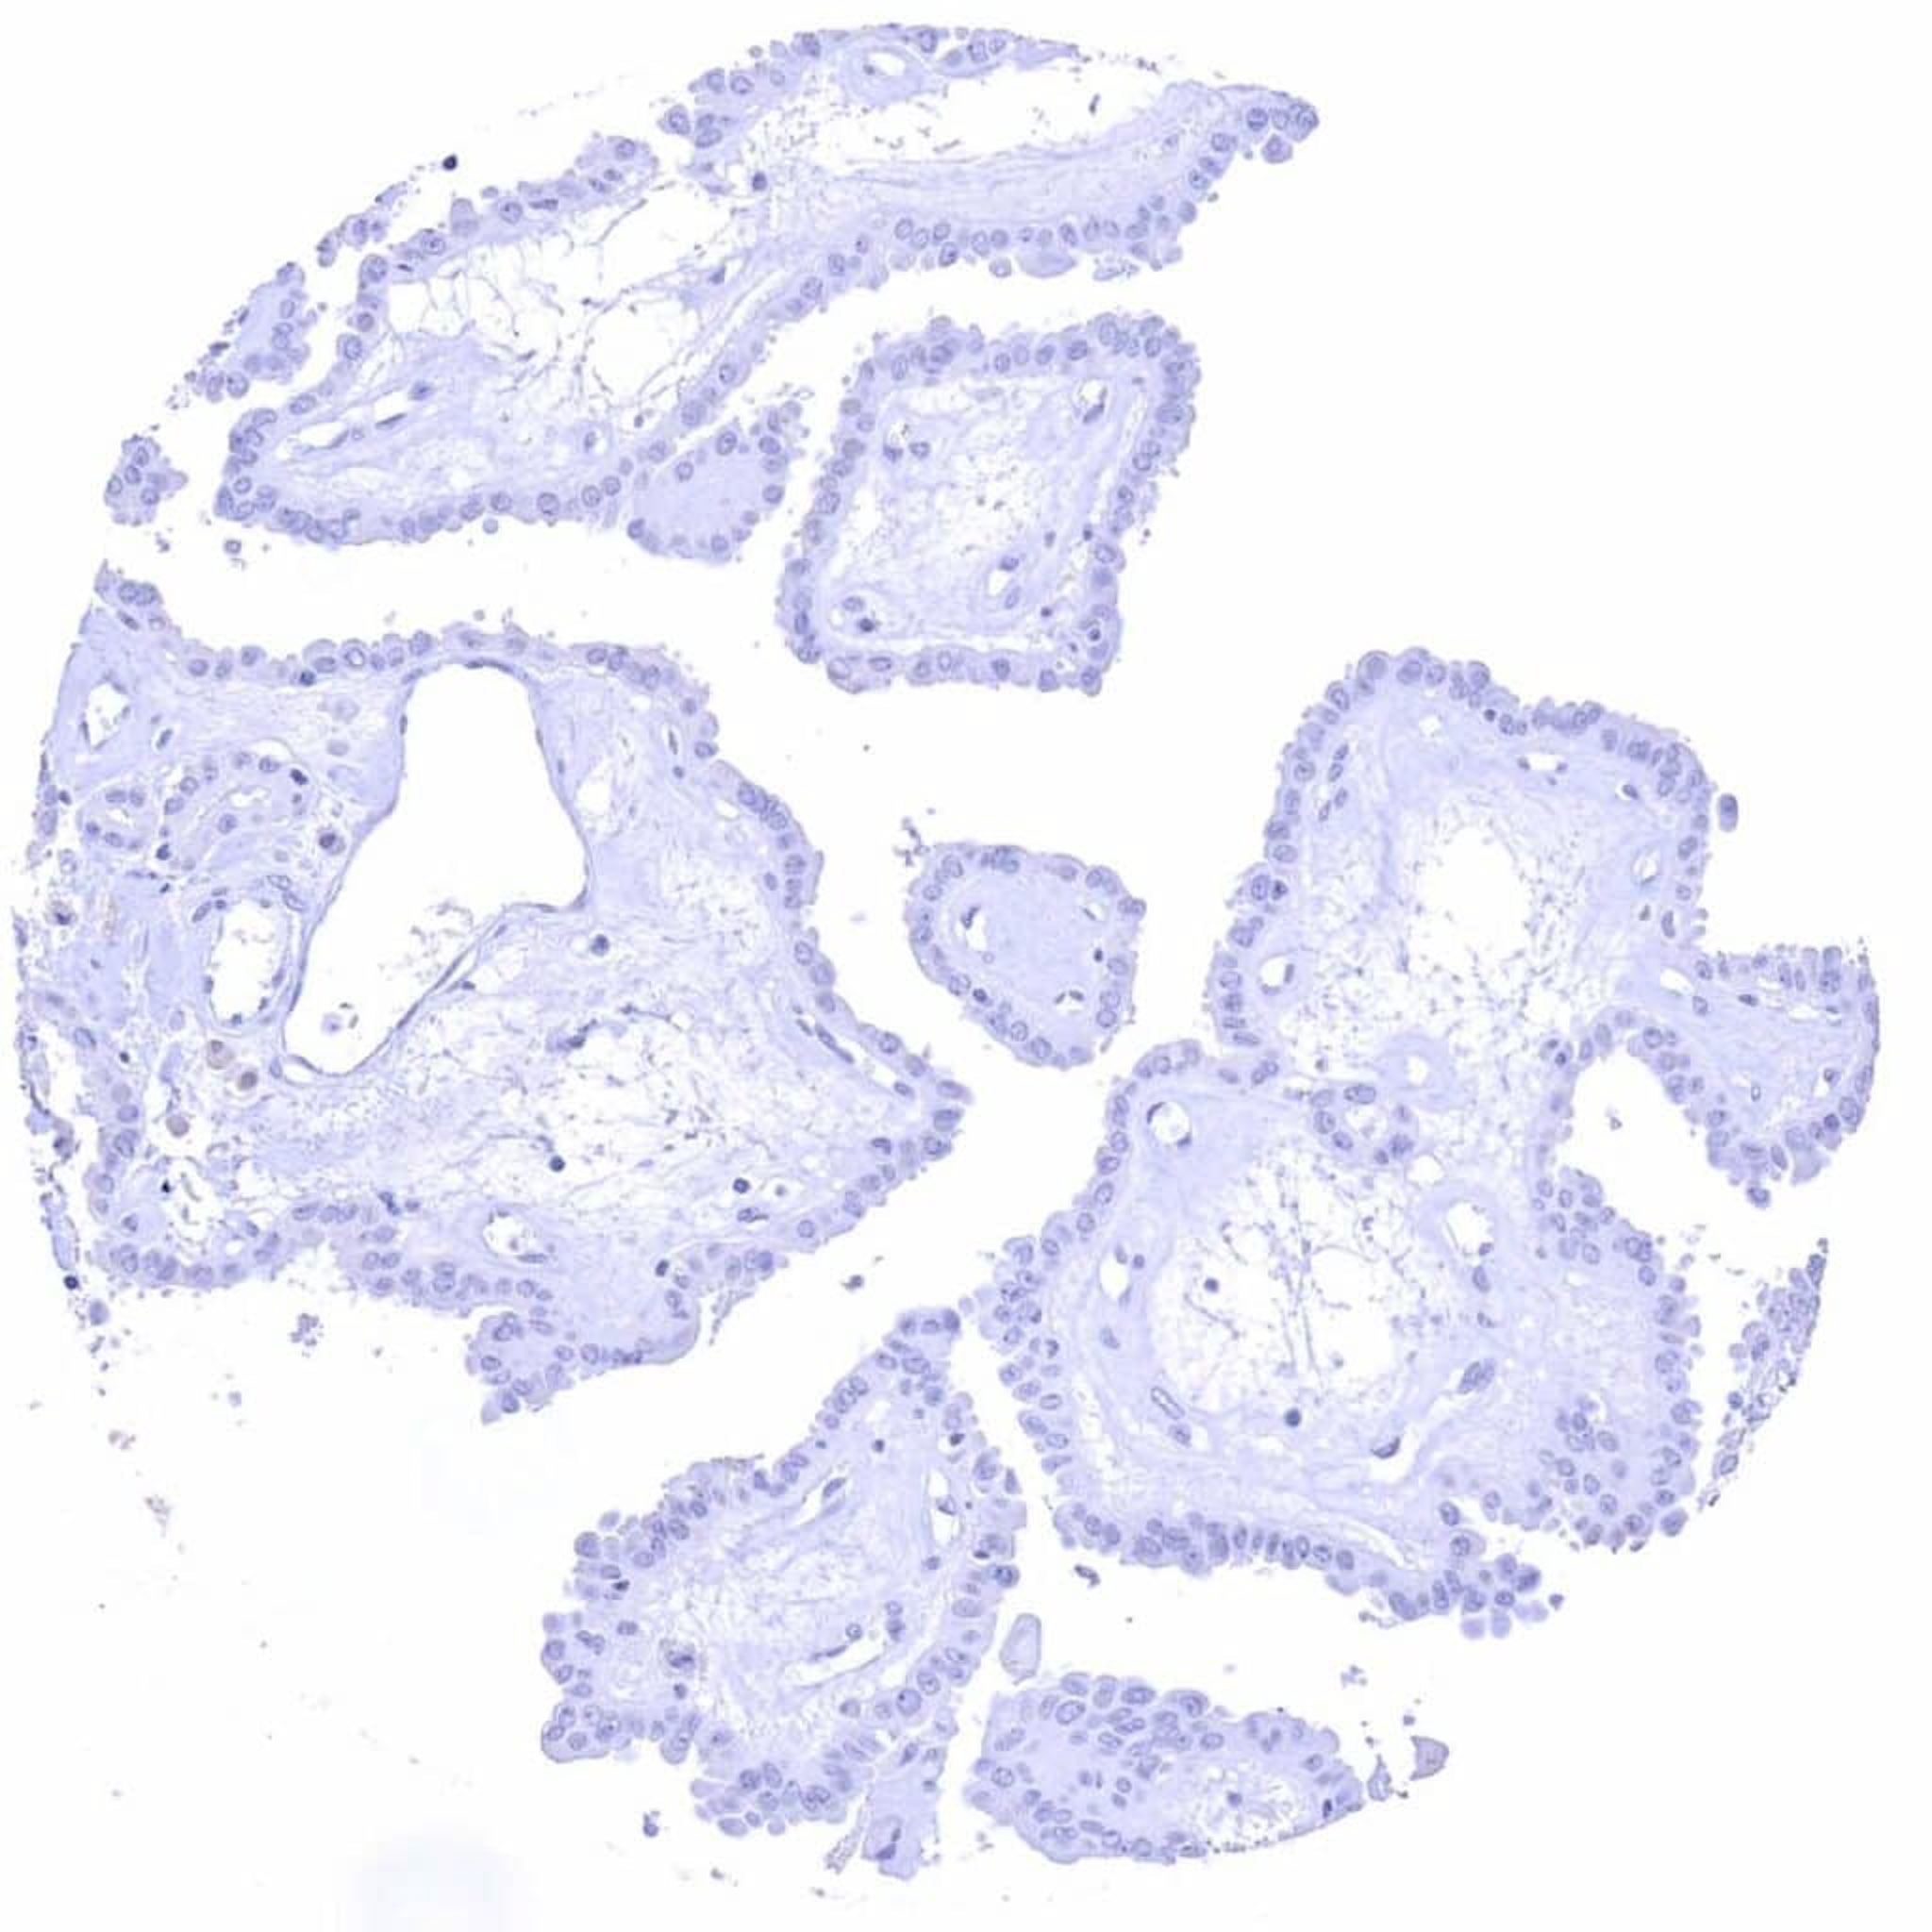

Prostate – C-peptide negative adenocarcinoma (Gleason 3+3=6)